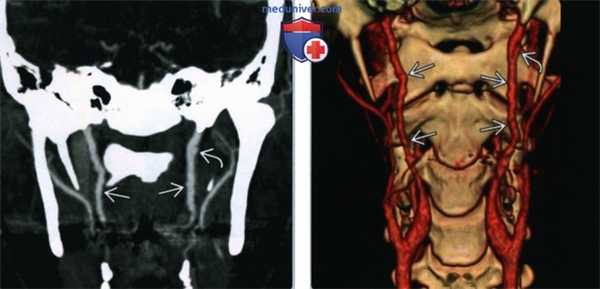

(Слева) КТ-ангиография, коронарная проекция. Женщина 44 лет с фиброзно-мышечной дисплазией: определяется нечеткость контуров обеих внутренних сонных артерий, которая весьма характерна для фиброзно-мышечной дисплазии. В левой сонной артерии имеется участок расслоения с формированием псевдоаневризмы.

(Справа) Объемное изображение, КТ-ангиография в коронарной проекции, эта же пациентка. Здесь аневризма левой внутренней сонной артерии видна более четко. Вновь можно увидеть неровные контуры обоих сосудов, которые характерны для фиброзно-мышечной дисплазии.